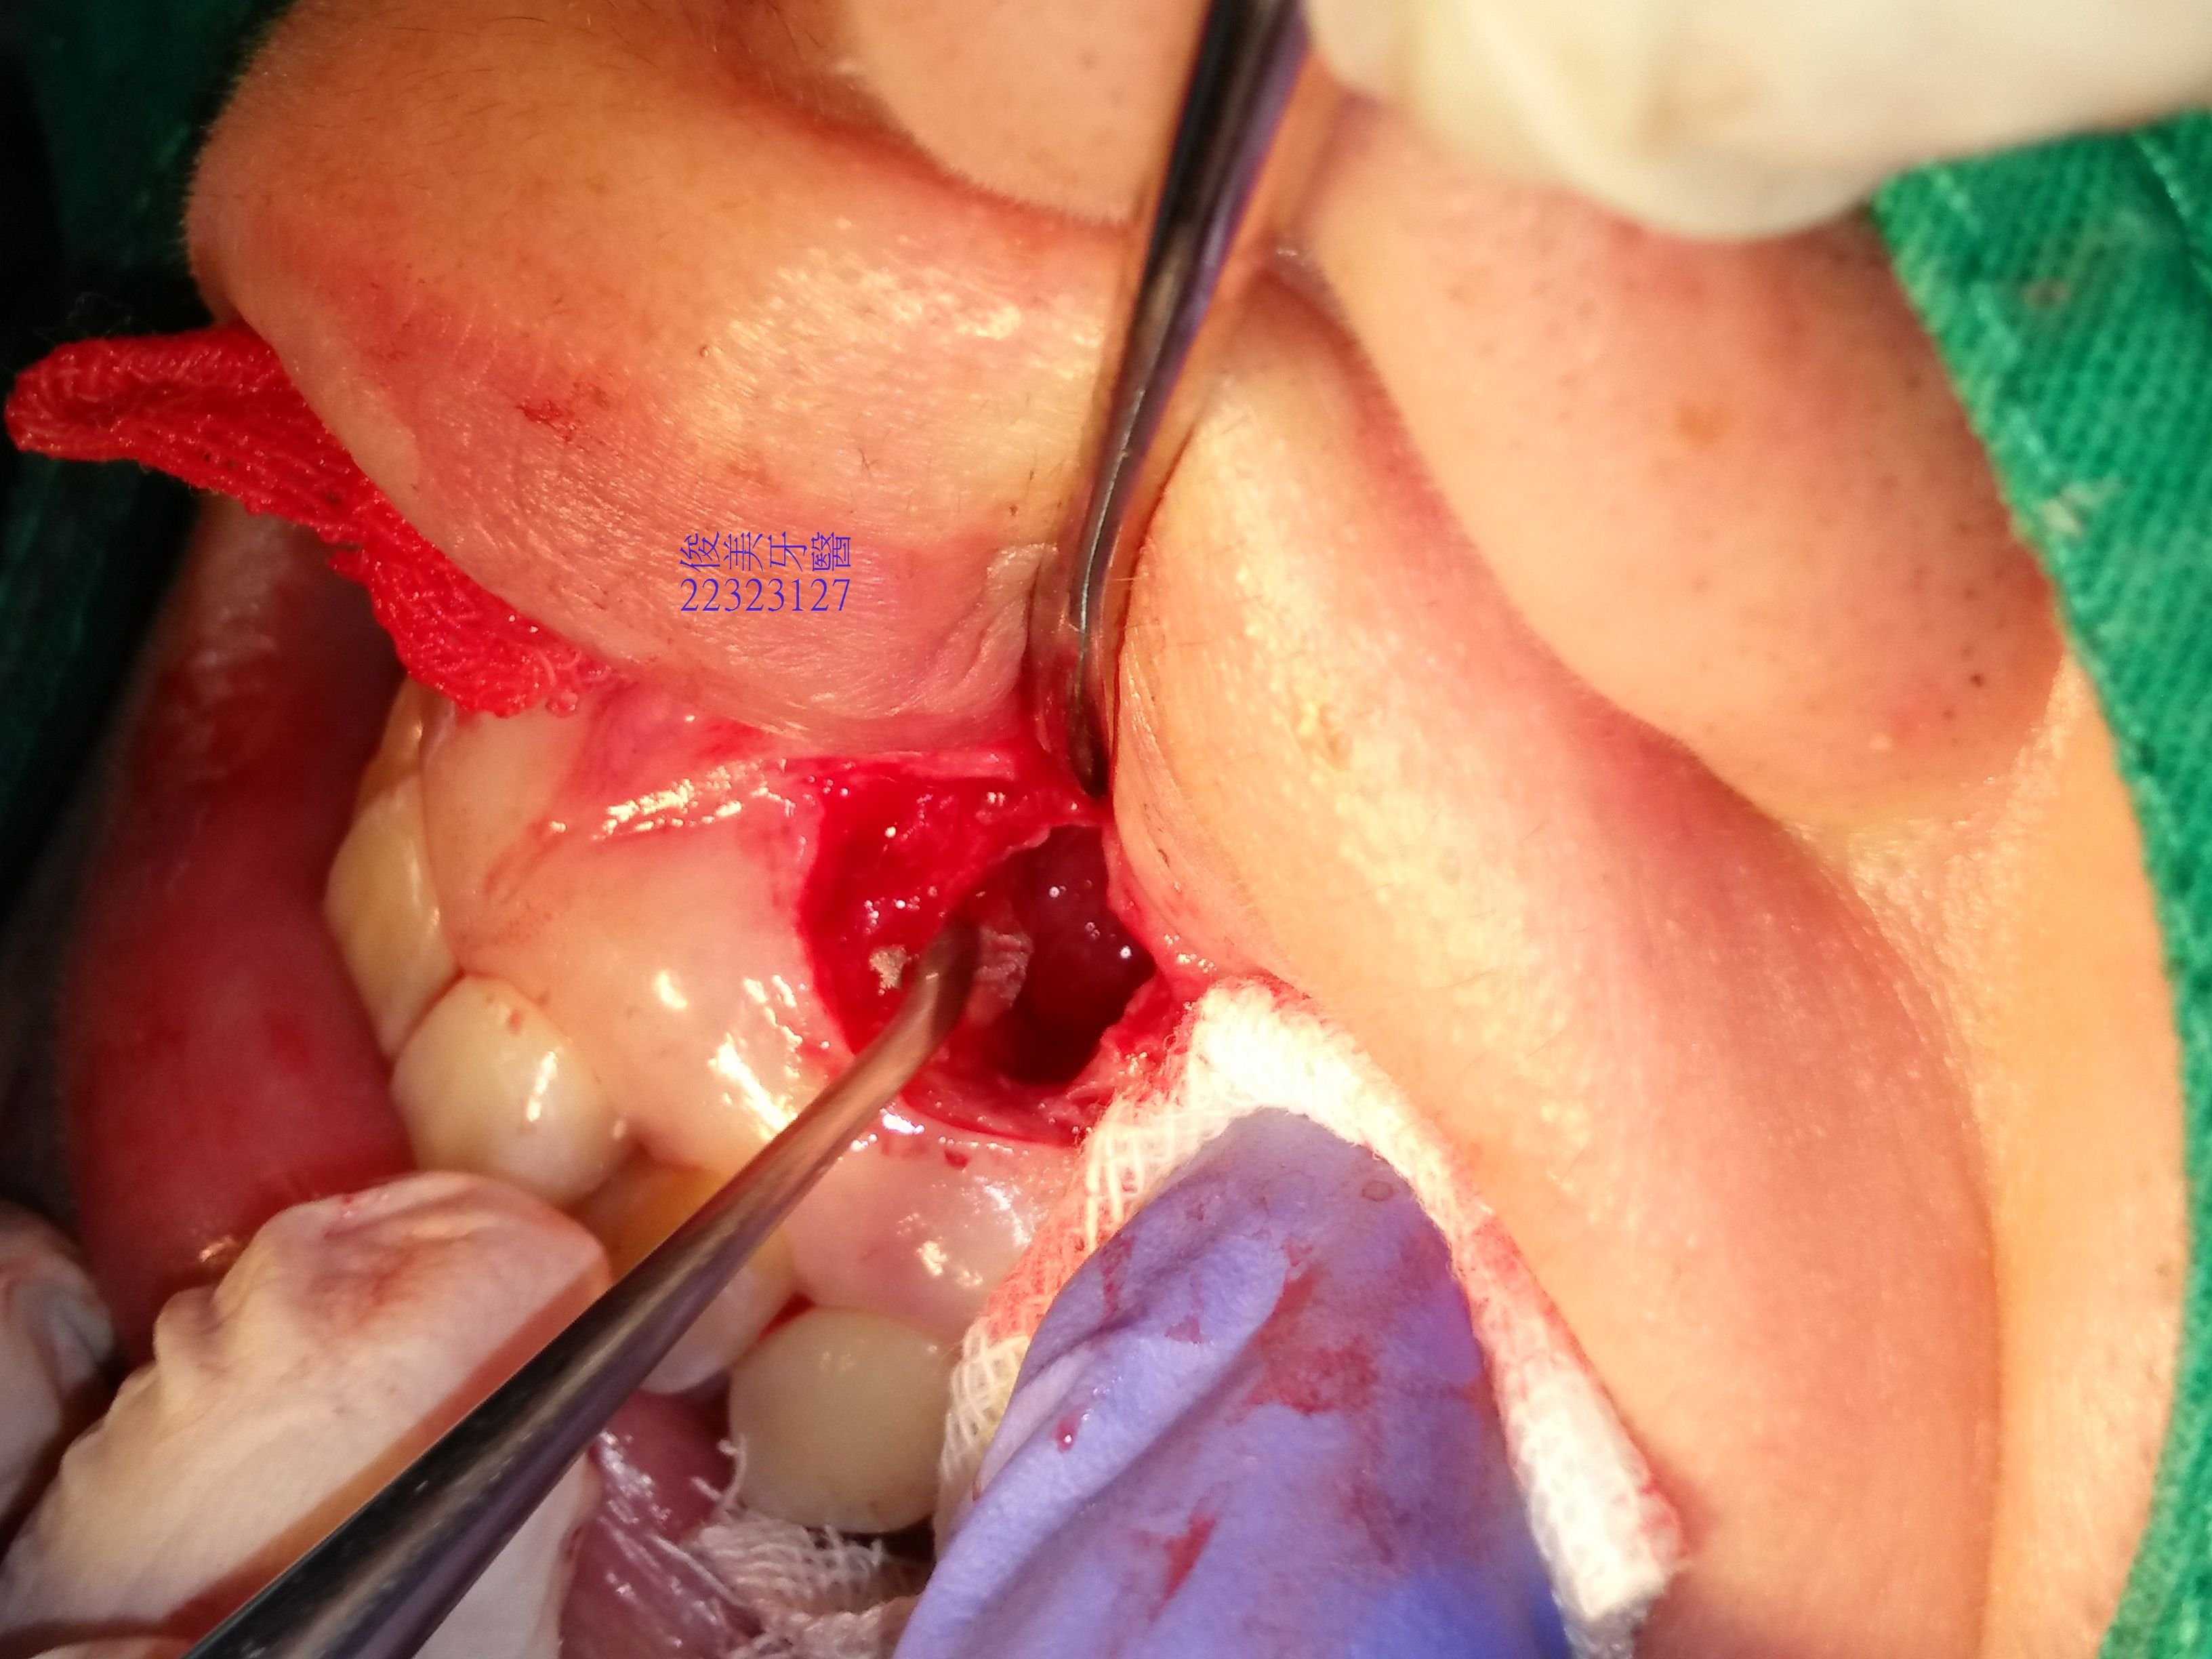

仔細將周圍清除乾淨。

填入人工骨粉。

及自體P.R.F幫助癒合。